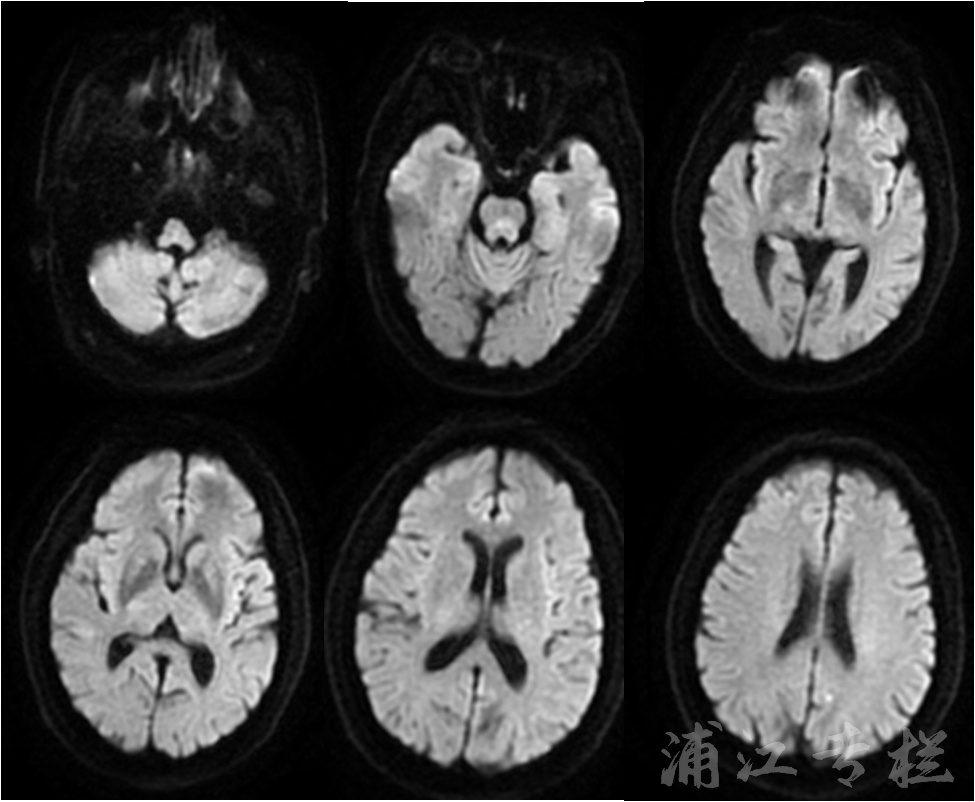

术后4天行磁共振DWI序列显示无新发脑梗。